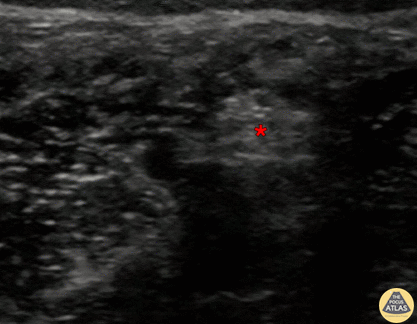

In-plane tibial nerve block, with needle seen entering from screen right (posterior), with injection of anesthetic superficial to the tibial nerve (*). The posterior tibial artery can be seen pulsating screen left of (anterior to) the nerve. Denver Health Ultrasound Fellowship